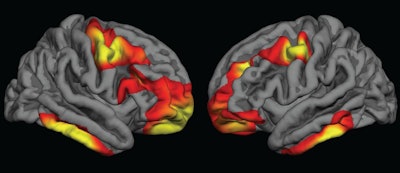

The researchers observed cortical thickness in the bilateral frontal and inferior temporal regions of the brain in adolescents who were exposed to folic acid compared with those who were not. For children born during the fortification period, partial folic acid exposure had more "intermediate effects," they noted.

The differences were characterized by significantly thicker brain tissue and delayed thinning of the cerebral cortex in regions associated with schizophrenia.

Colored areas indicate regions of the cerebral cortex that are significantly thicker in children who were exposed to folic acid fortification during pregnancy, compared with those who were not exposed. Images courtesy of Dr. Joshua Roffman.

Colored areas indicate regions of the cerebral cortex that are significantly thicker in children who were exposed to folic acid fortification during pregnancy, compared with those who were not exposed. Images courtesy of Dr. Joshua Roffman.Within the MGH cohort of normal brain scans, the researchers "observed widespread increases in frontal and temporal cortical thickness between comparable groups of youths who gestated just after, compared with just before, the rollout of folic acid fortification," they wrote. "Youths who gestated during the [folic acid] rollout, and who therefore had partial exposure, demonstrated intermediate increases, consistent with a dose association."

Results from the PNC subjects were similar to those in the MGH adolescents, with individuals exposed to folic acid fortification showing signs of delayed cortical thinning of similar duration in the frontal, temporal, and parietal regions.